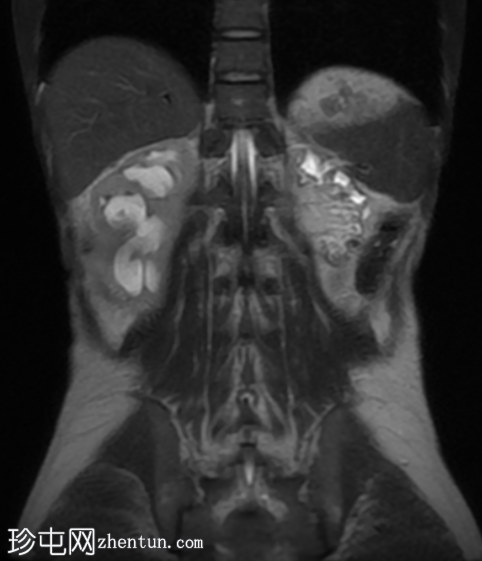

MRI

冠状位

T2加权像

再次观察到上述肾前部外生性病变,其实性成分在T1加权像上呈等高信号,在T2加权像上呈低信号,伴有碎片扩散受限和低ADC值(化脓性物质)。囊性成分内部可见液-碎片/脓液界面。可见内部低信号结石。可见肾周模糊影。该病变压迫并可能侵犯右肾盂,导致中度肾积水。

病灶不规则的低信号,以及液-液界面伴有碎屑(可能为化脓性物质)扩散受限和肾周模糊,再次高度提示炎症性病变(黄色肉芽肿性肾盂肾炎,XGP),而非可能性较小的肿瘤。

左肾萎缩,体积较小,内含多发低信号结石。